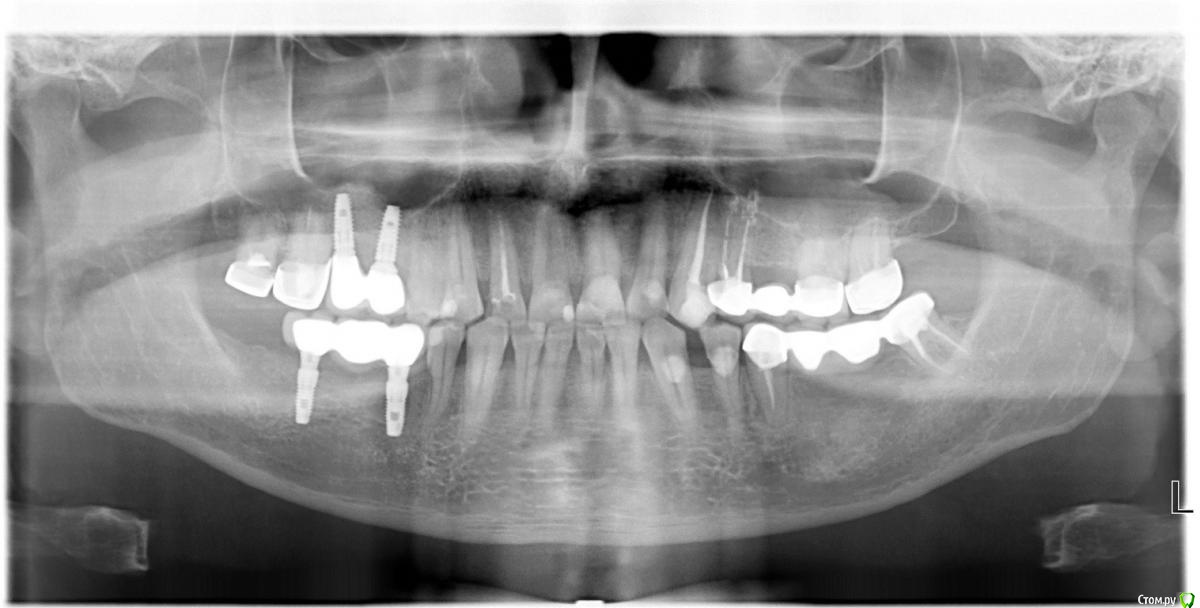

vpaoli Опубликовано 15 октября, 2018 Поделиться Опубликовано 15 октября, 2018 Здравствуйте,помогите выбрать план лечения.Левая сторона (противоположная от установленных имплантов), верхняя челюсть. Мост , покрывающий 3 зуба слетел, потому что крайний предпоследний (6-й) зуб отломился. 4-й зуб моста в нормальном состоянии. 3-й зуб (клык) потемнел и я хочу ставить на него коронку. От 6-го зуба остался только корень. Сам думаю над таким вариантом :1) Поставить мост на 3-й, 4-й зубы + искуственный зуб (т.е. коронка на 3 единицы).2) 6-й зуб удалить и на его место поставить имплант . Мой вариант в определенном смысле экономичный т.к. ставить придется только 1 имплант. Как вам такой вариант ? Покритикуйте, предложите альтернативу.Нужно делать синус-лифтинг открытый или нет ? Справа стоят импланты и делался открытый синус-лифтинг, так решил доктор. Панорамный снимок прилагается. Спасибо. Ссылка на комментарий

vpaoli Опубликовано 15 октября, 2018 Автор Поделиться Опубликовано 15 октября, 2018 по п..1 предполагается, что искусственный 3-й зуб коронки будет "висящим". Уж не знаю, делают так или нет. Ссылка на комментарий

DoctorT Опубликовано 16 октября, 2018 Поделиться Опубликовано 16 октября, 2018 Если 6 зуб на удаление, то консольному протезу однозначно отказать, В дальнейшем дороже выйдет. " Коронки и 2 имплантанта в позиции 5 и 6. Ссылка на комментарий

vpaoli Опубликовано 16 октября, 2018 Автор Поделиться Опубликовано 16 октября, 2018 Если 6 зуб на удаление, то консольному протезу однозначно отказать, В дальнейшем дороже выйдет. " Коронки и 2 имплантанта в позиции 5 и 6. Спасибо. Видимо так и будет.2 импланта обьединенные мостом или каждый имплант со своей коронкой ? Ссылка на комментарий

DoctorT Опубликовано 17 октября, 2018 Поделиться Опубликовано 17 октября, 2018 Спасибо. Видимо так и будет.2 импланта обьединенные мостом или каждый имплант со своей коронкой ?Я бы сделал на имплантантах вместе, а на своих зубах по отдельности. Ссылка на комментарий